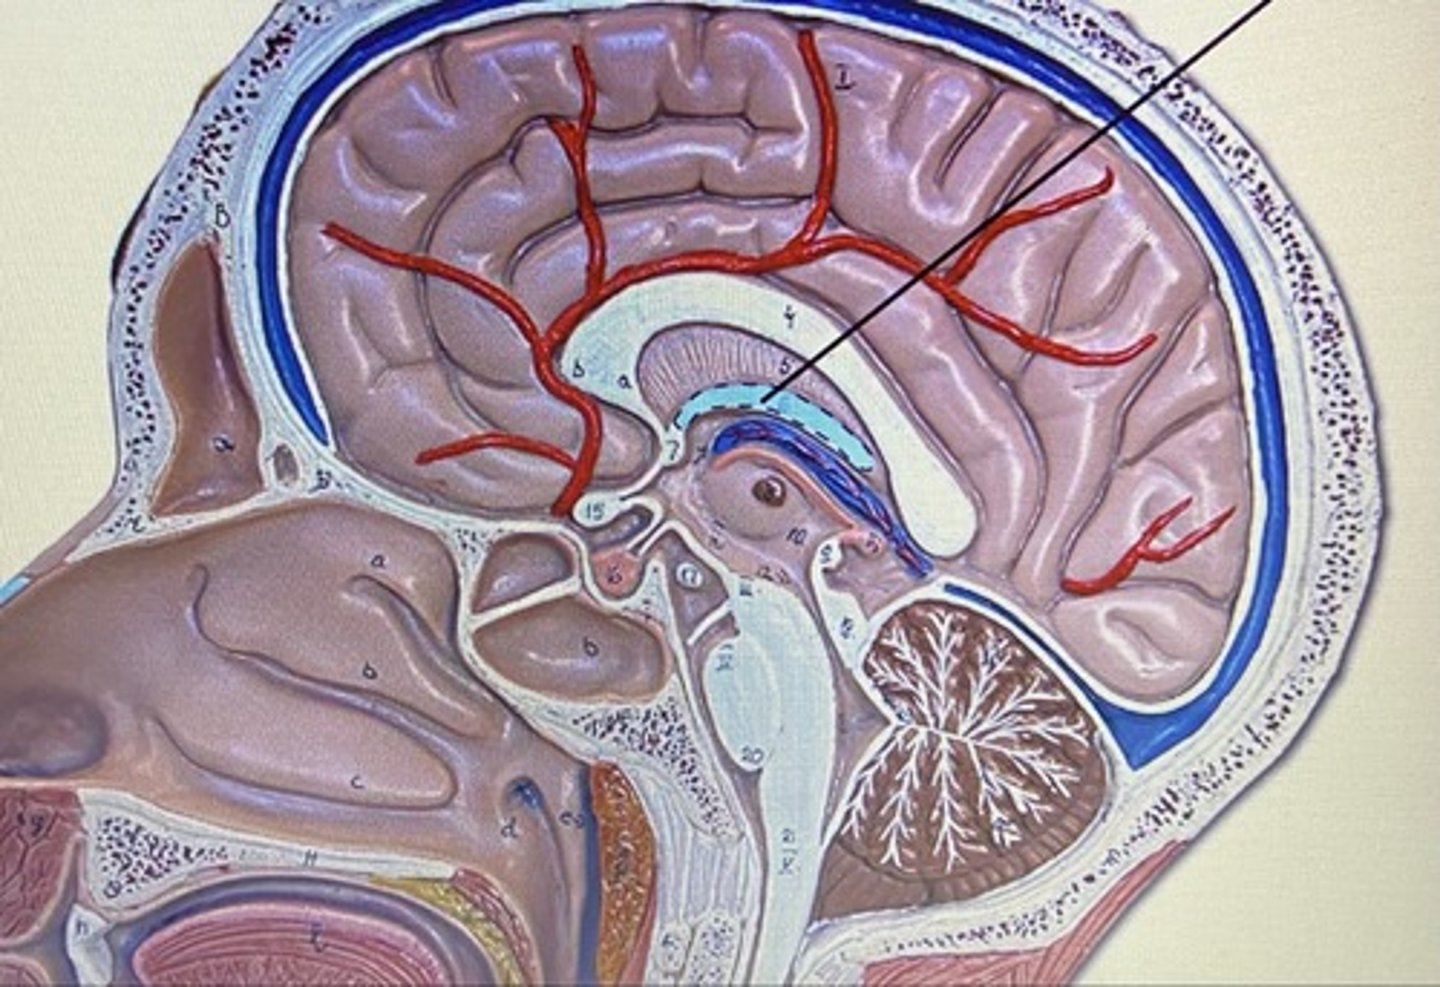

Frontal Lobe

Parietal Lobe

Temporal Lobe

Occipital Lobe

Cerebrum

Cerebellum

Pineal Body/Gland

Corpus Callosum

Choroid Plexus

Fornix

Thalamus

Hypothalamus

Infundibulum

Pituitary Gland

Olfactory Bulb

Olfactory Tract

Superior Colliculus

Inferior Colliculus

Lateral Ventricle

Third Ventricle

Fourth Ventricle

Cerebral Aqueduct

Meninges

The three protective membranes

-dura mater

-pia mater

-arachnoid

Dura Mater

Arachnoid Mater

Pia Mater